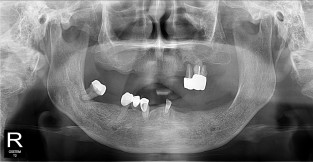

• 9

무치악

치료기간 : 2023-02-21 ~ 2023-10-21

1. 상기 x-ray 이미지 모두 동일한 해당 의료기관에서 진료한 환자입니다.

2. 상기 x-ray 이미지 모두 동일 인물의 것입니다.

3. 치료 전 이미지는 2023-02-21에 촬영했으며, 치료 후 이미지는 2023-10-21에 촬영하였습니다.

4. 상기 x-ray 이미지 모두 동일 조건에서 환자분의 동의를 받아촬영되었습니다.

* 임플란트 시술은 환자분의 상태(고혈압, 당뇨 등)에 따라 부작용이 있을 수 있으니, 반드시 전문의와 상담이 필요합니다.

* 임플란트 수술 부작용

: 수술 후 출혈, 교합, 통증, 붓기, 염증 등의 문제점이 발생할 수 있습니다.)